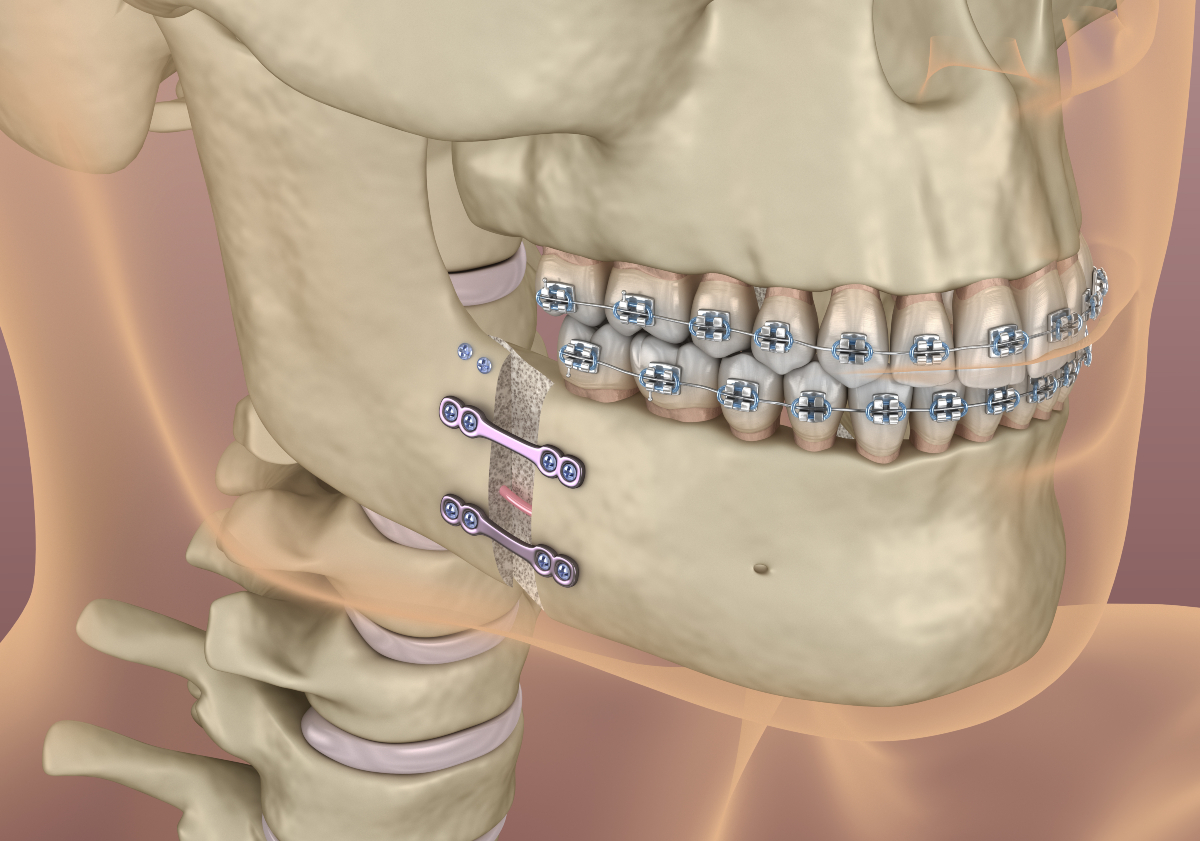

What is orthodontic or "orthognathic" surgery?

Orthognathic surgery—also known as corrective jaw surgery—is a collaborative procedure that combines orthodontics with oral surgery to correct misalignments in the jawbones that can’t be addressed with braces or Invisalign alone. This type of surgery may be recommended for adults or teens dealing with issues like chronic jaw pain, facial asymmetry, difficulty chewing, or obstructive sleep apnea. By realigning the jaws, we’re not just improving the bite—we’re enhancing function, health, and facial harmony in a lasting way.

Improved bite & function

By correcting underlying skeletal imbalances, orthognathic surgery can dramatically improve your ability to chew, speak, and breathe comfortably.

Facial balance & aesthetics

Surgical jaw correction enhances facial symmetry and balance—often with subtle but powerful changes that bring harmony to your profile.

Long-term health benefits

Aligning the jaws can help relieve TMJ discomfort, reduce chronic headaches, and even address sleep-related issues like snoring or sleep apnea.